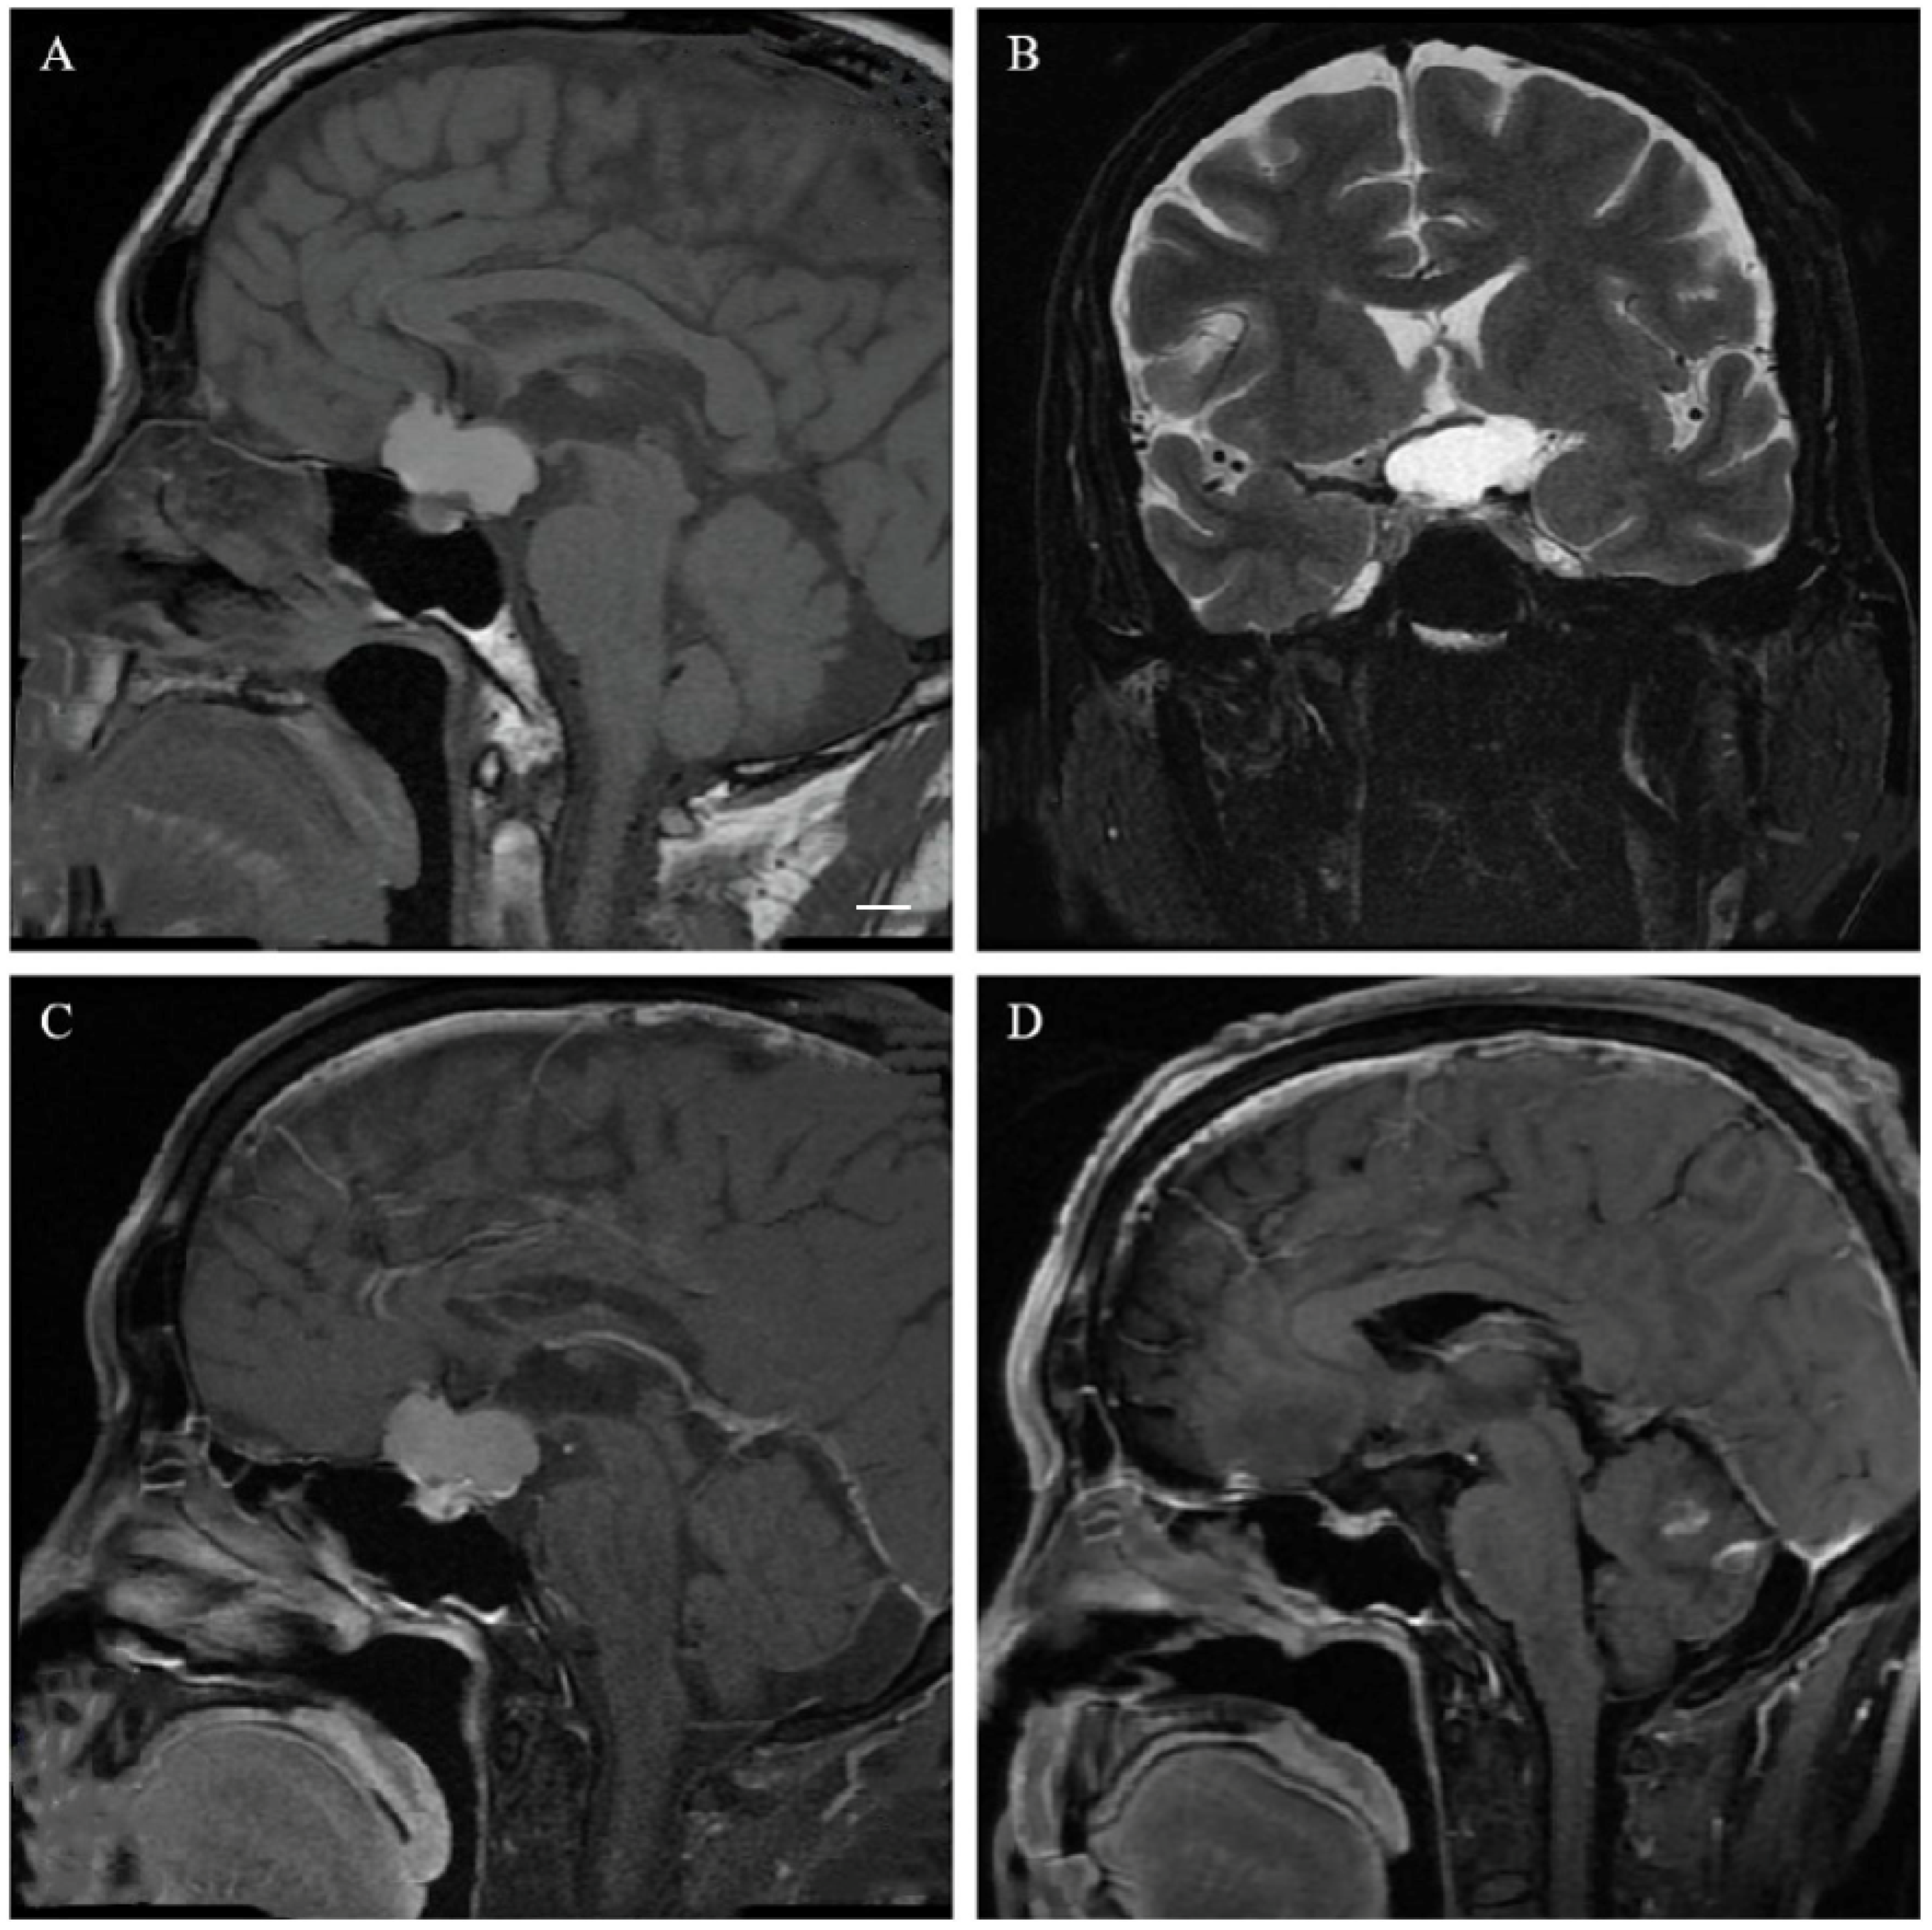

2.3. Neuroradiological Evaluation

3.2. Neuroradiological Features